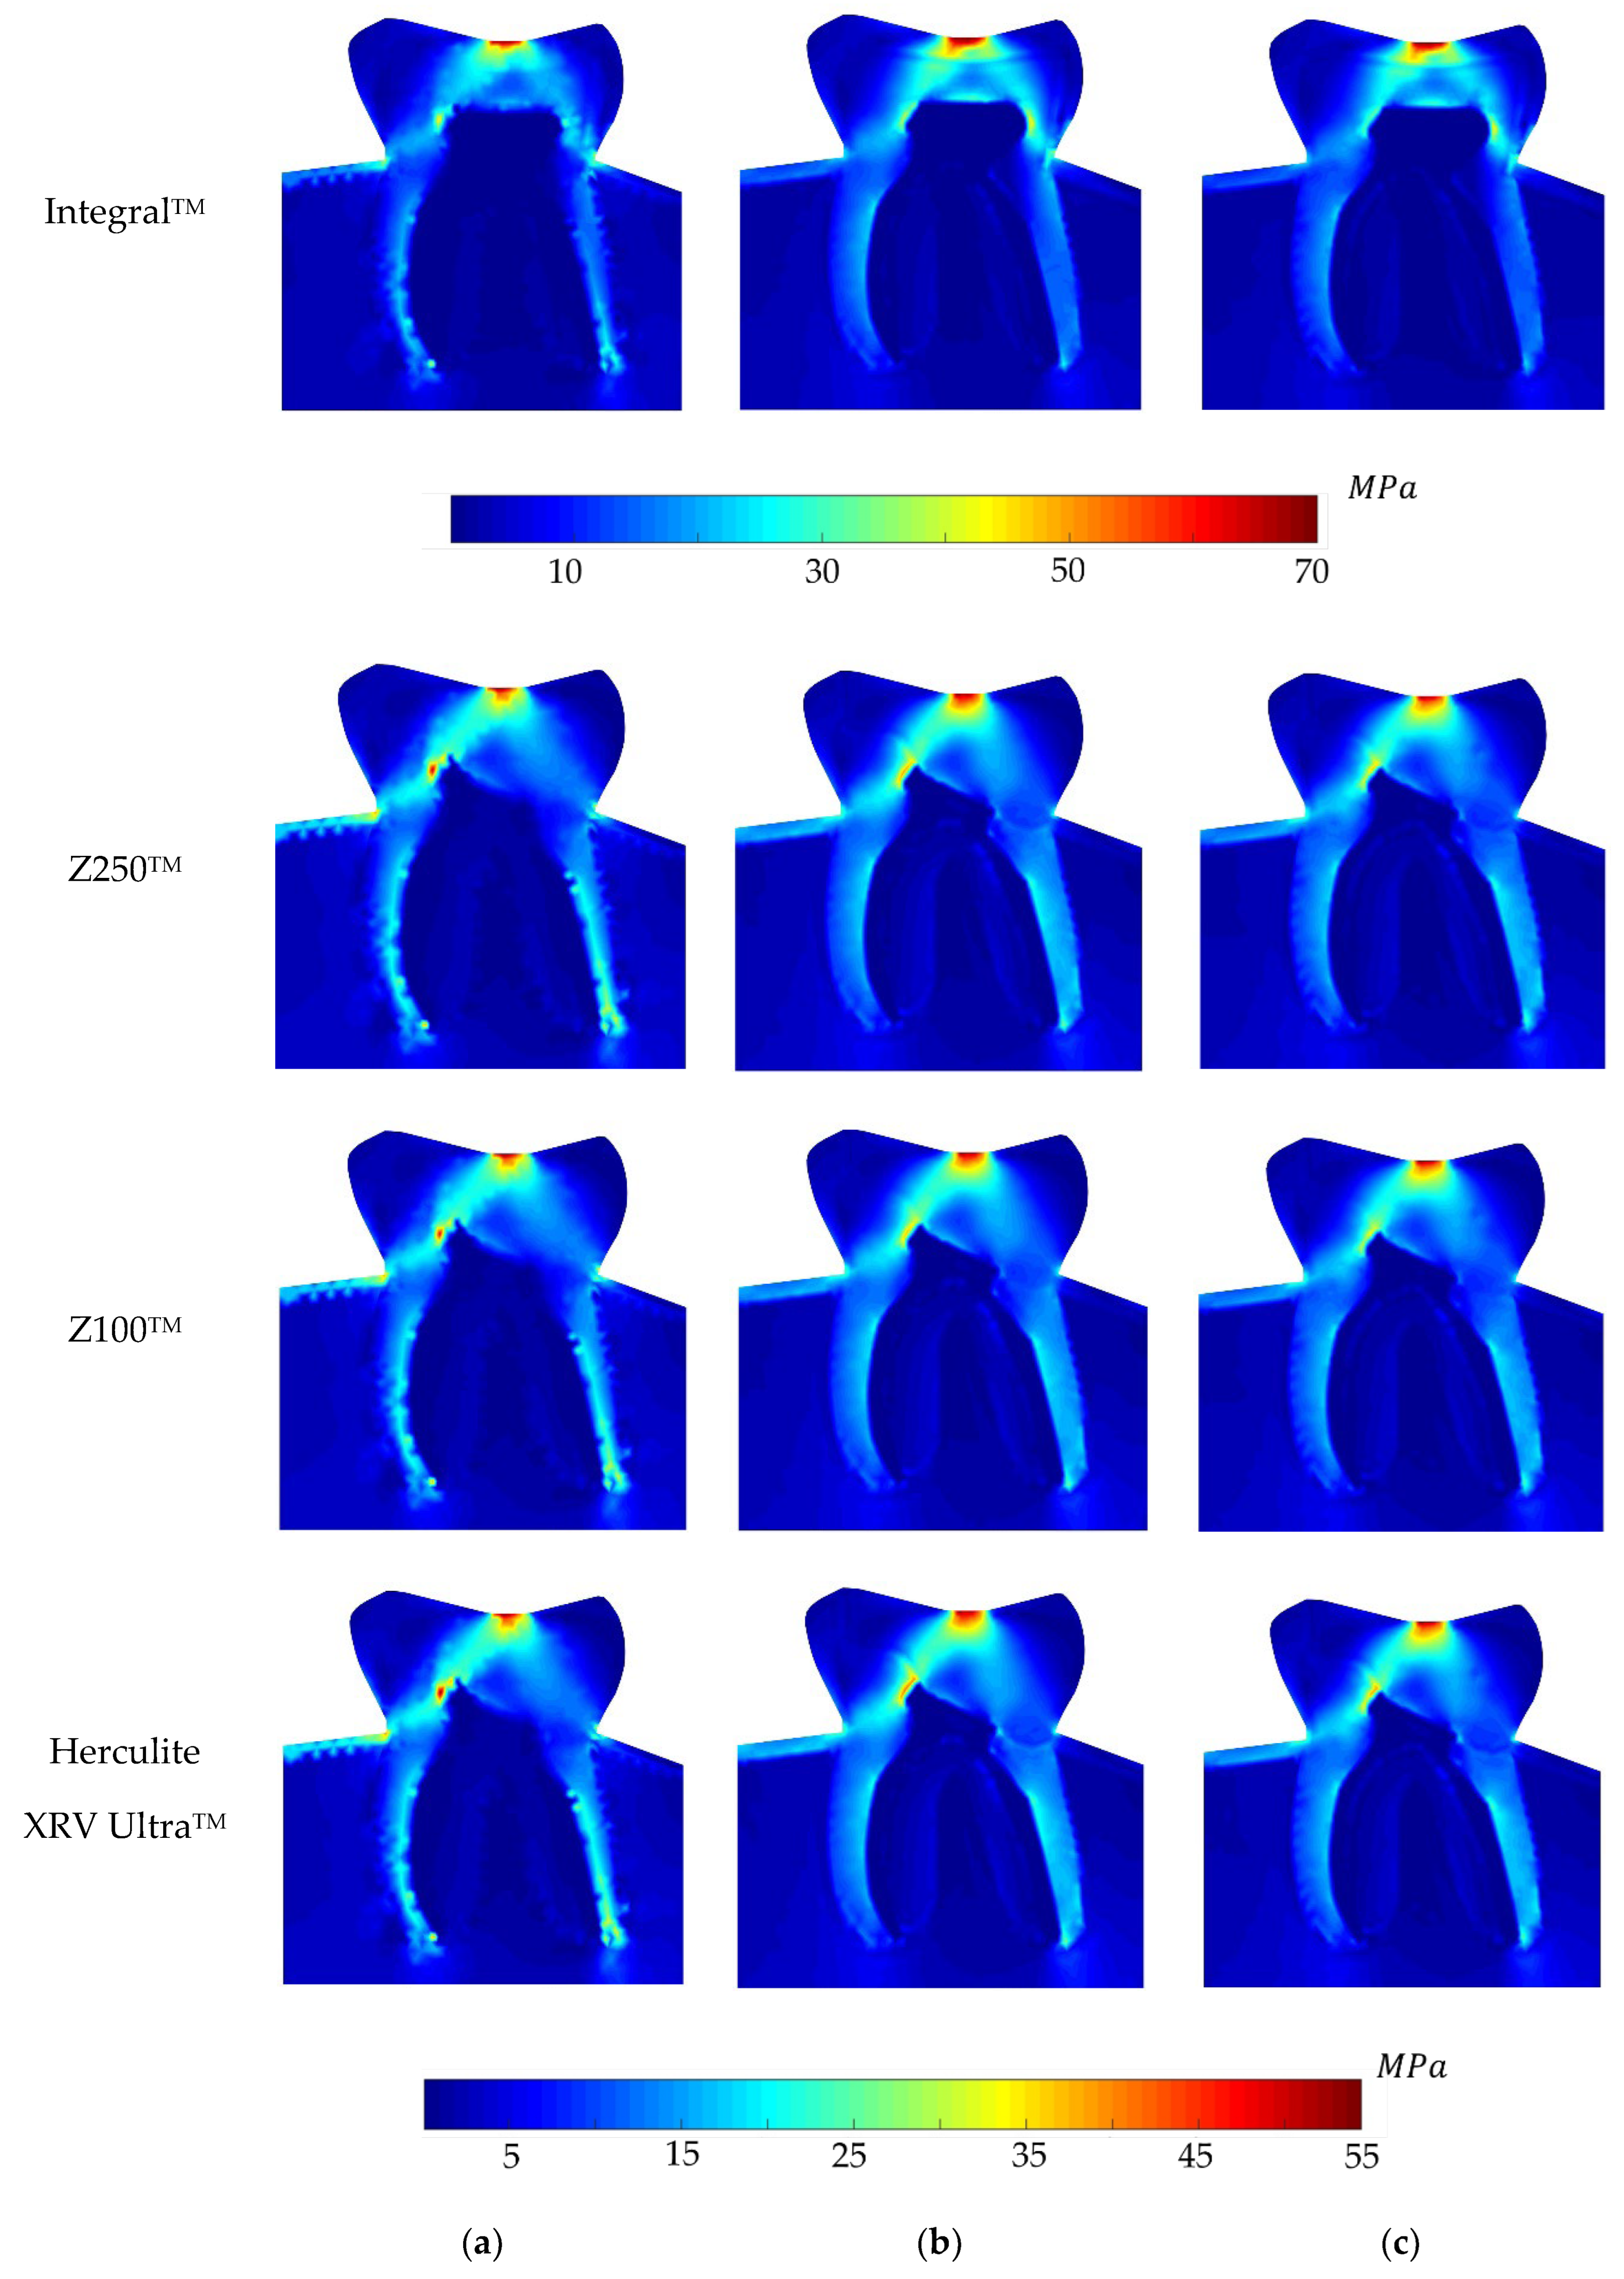

5. Analysis and Results

6. Discussion on the Results

- The non-restored tooth is characterised by enamel rather than composite restoration. Enamel exhibits the highest Young’s modulus compared to the composites. Consequently, an integral tooth demonstrates a greater ability to withstand forces compared to composite restorations. It means that the stiffness of enamel is higher than that of the restorative materials.

- The ranking on the local stress analysis can be rationalised based on the superior mechanical properties of Z100TM, including its elevated Young’s modulus, notably higher tensile and compressive strength compared to other composite materials. This implies that dental restoration using Z100TM results in increased stiffness and rigidity in the treated tooth. It owns the highest percentage of fillers, 66%, which implies higher hardness.

- Herculite XRV UltraTM exhibited the weakest response in terms of elasto-static analysis. One potential reason could be attributed to its lower Young’s modulus and consequently, the lowest hardness, which may be influenced by the presence of barium glass filler in this composite. Conversely, the Zirconia Filler in Z100TM and Filtek Z250TM might account for the improved physical properties observed in these two composites.

- In the depicted stress profiles of the BLV load case, where there is no tooth on the left side of the model (no essential boundary condition), the stress distribution shows higher value on critical regions, mostly close to the boundaries. The absence of essential boundary conditions on the left side of the 2D model in the BLV and OLV load cases leads the applied force to produce a higher level of stress on the borders and critical spots. In this regard, the global stress distribution maps obtained with the meshless methods clearly show the potential rupture lines. This study shows the importance of the neighbour tooth to prevent a potential fracture.